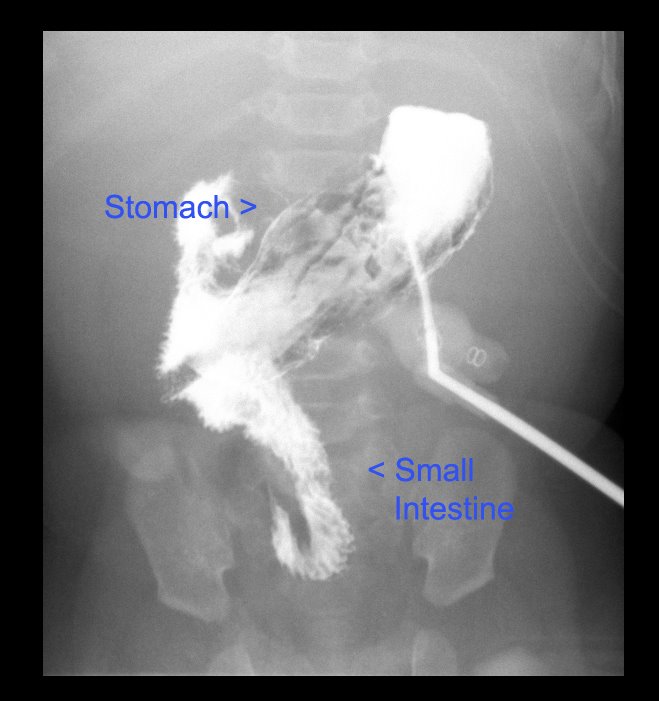

We had misunderstood what we’d been told about the placement of the line. The azygus vein is not a central vein. That means, it doesn’t directly connect to the heart. The tip of the new line is in a dilated part of that vein. But, after the tip there are some collateral (spiderlike veins that grow around a clot to reroute bloodflow like the little streams that form around the sides of a river if it is partially blocked.) And it is those that are connecting to the main veins and to the heart.